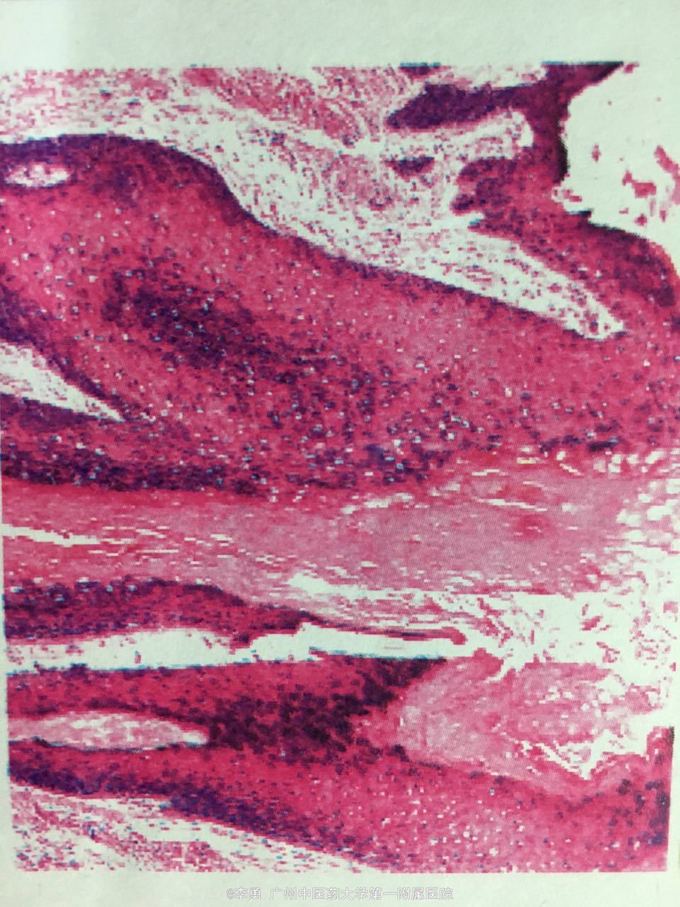

口周、四肢多发淡红斑基础上的浅溃疡、结痂,周围可见溃疡愈合后遗留的萎缩性疤痕、色素脱失。 病理活检:表皮增生、增厚伴轻度角化过度及角化不全,局部见浆痂,毛囊见明显角质栓形成,皮脚延长,真皮乳头部及浅层胶原变性,伴散在慢性炎细胞浸润。